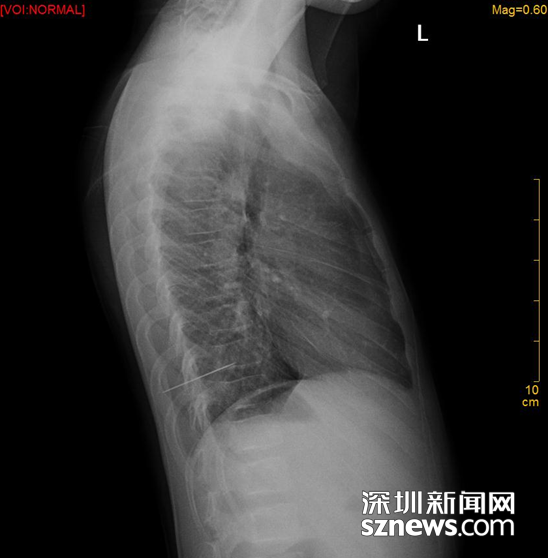

CT片中针清晰可见

钟医生从手术室匆匆赶来,接过“小明玉”的CT片子,只见针部分插入肺内,出现肺挫伤。

但是,“小明玉”还没有完全脱离风险。经CT检查,确认肺部被扎伤,有少量出血,所幸没有扎穿肺部及大血管。医生这才宣告,“小明玉”已无性命之忧。